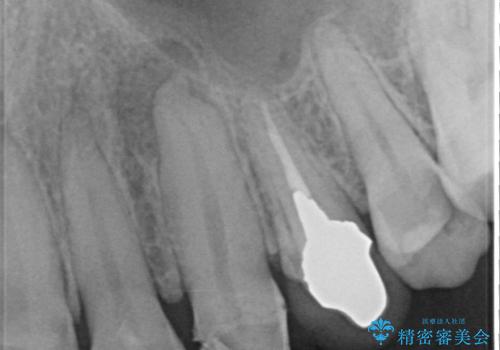

▶左上犬歯

根管治療行い感染除去した後、最終補綴はオールセラミッククラウンにて審美的に